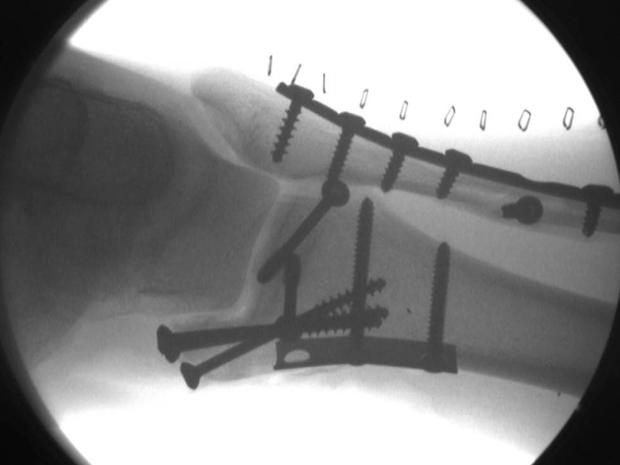

Watch those nail guns. This worker didn't, and he wound up shooting a nail into his hand. Doctors removed it, and he was fine.